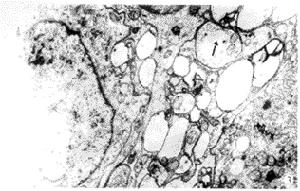

4.超微結構改變在NCL的超微結構檢查可以發現5種不同的嗜鋨性脂褐素顆粒,包括常規脂褐素、顆粒脂褐素、曲線體指紋體和微管聚集。單獨依靠脂褐素的出現不能對NCL進行可靠的分型,但在NCL不同亞型的表現形式是不一樣的,顆粒脂色素出現在嬰兒型NCL,線樣體和指紋體分別出現在晚期嬰兒型和青少年型,極少有顆粒脂色素出現在青少年型患者,成年型NCL為混合型脂褐素顆粒。血淋巴細胞和小汗腺分泌部上皮細胞的超微結構檢查更有助於NCL的診斷和分型,在小汗腺分泌部上皮細胞和淋巴細胞內顆粒脂色素出現在嬰兒型、線樣體出現在晚期嬰兒型指紋體出現在青少年型,青少年型患者存在不同形態的指紋體結構,這些特徵性的脂褐素顆粒需要在放大2萬倍才能觀察清楚,此外不要把正常的生理性脂褐素誤為病理性脂褐素。